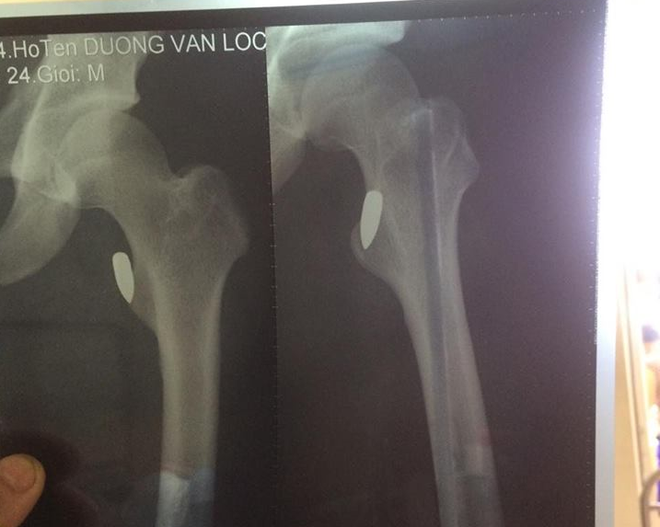

Bác sĩ tại Bệnh viện Lạc Việt (Vĩnh Phúc) cho biết, kết quả phim chụp X-quang cho thấy anh Lộc bị trúng đạn, rất may đầu đạn chỉ đi vào phần mềm, còn cách xương chỉ vài milimét.

Vĩnh Phúc: Vận động viên võ thuật Pencak Silat bị trúng đạn sau buổi tập - Ảnh 2.

Hình chụp vết thương của nạn nhân

Do vết thương khá phức tạp nên sau khi sơ cứu, anh Lộc được chuyển xuống viện Bạch Mai rồi chuyển sang Việt Đức để mổ gắp đầu đạn ra ngoài.

Tuy nhiên, đến giờ các bác sĩ vẫn chưa thể mổ để gắp đầu đạn vì tổn thương do đạn bắn gây ra khá nghiêm trọng, đầu đạn nằm sâu, gần xương nên chưa thể can thiệp ngay.